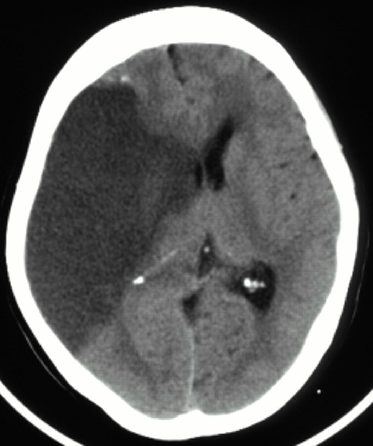

The most likely cause of acute deterioration 2 days after a completed large territory stroke is cerebral edema. The CT demonstrates a large right MCA infarct associated with mass effect and midline shift from cerebral edema. No sign of hemorrhage is present on the CT scan. The patient presented outside the window for intravenous recombinant tissue plasminogen activator (tPA) or endovascular therapy. Therefore, hemorrhagic conversion and reperfusion are unlikely causes of his mental status change